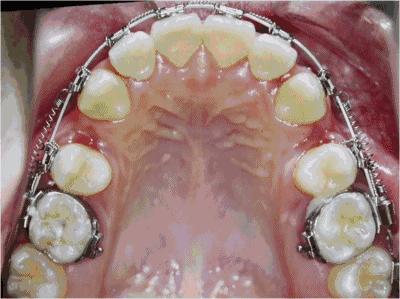

牙齿正畸是医生通过矫治器给牙齿一个外力,从而让牙槽骨发生改建,带动牙齿移动。但很多人的口腔存在着牙骨量不协调的问题,也就是说,牙齿量大于骨骼量,牙齿的周长大于颌骨的周长,导致牙齿拥挤和排列不齐等问题。

所以,如果是这样的情况,就需要通过拔牙来挪出空间让其他牙齿移动,最终排列整齐,进而改善咀嚼功能、让面型更好看。

反之,如果不拔牙的情况下,无法改善功能、提升美观,那就需要拔牙。因为矫治拔牙是矫正一些错颌畸形必须采取的步骤,依错颌种类与程度的不同,有些错颌完全不必拔牙,而有些错颌非拔牙不可。

一般而言,牙齿矫正需拔牙时,以双尖牙为优先考虑,有些情况下可选择拔下颌门牙、蛀牙或坏损较严重者。当然,如果您想不拔牙或者少拔牙,也可以告知主治医生,医生会根据实际情况适当调整矫治方案,或者选择其他矫治方式,以达到理想效果。